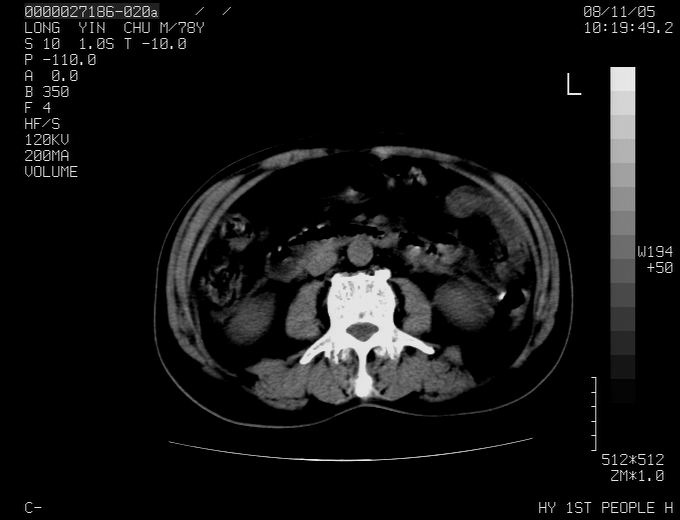

标题: CT16532:M78Y,肝脏病变,请会诊 [打印本页]

标题: CT16532:M78Y,肝脏病变,请会诊

腹胀,腹痛就诊,男性,78岁,外院b超未见异常。

肝ca,脾肾转移

支持脾肾转移瘤,双侧胸腔积液。

考虑弥漫性肝癌并脾及双肾转移.双侧胸水.

图片质量欠佳:多考虑:左侧肾癌。脾脏转移!胸膜转移!

肝脾肾转移瘤可能性大,左肾不除外梗塞,双侧胸水

考虑肝癌并双肾及脾脏转移;双侧胸腔积液。